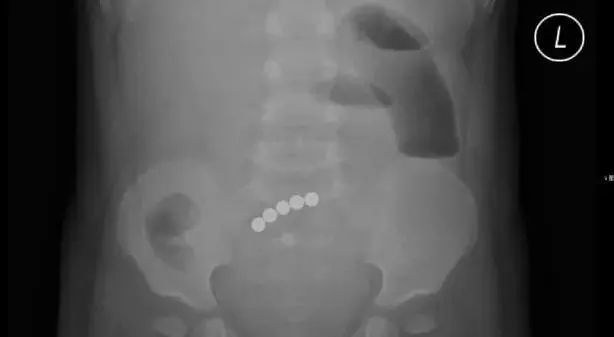

X光检查发现,小静腹中有5颗小球

居然在小静肚子里发现,有5个连成圈的小球!

打开腹腔后,医生终于找到了磁力球排不出来的原因:这5个小球分布在不同的肠段,但却牢牢地吸在一起。

医生小心地取出小磁球,再把穿孔的肠道切除,最后进行了缝合。整个手术足足花了2个小时。